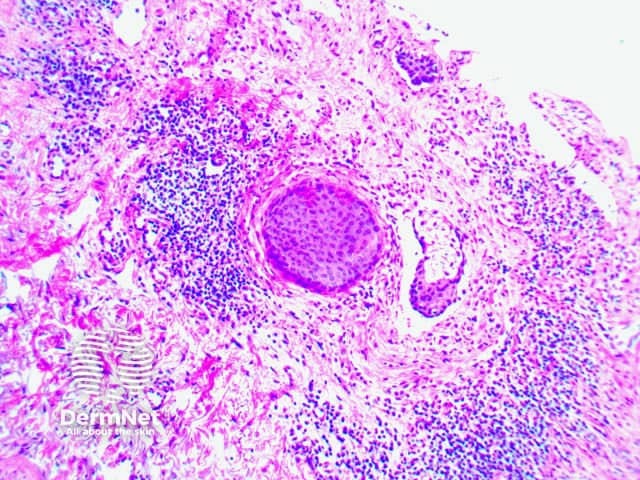

Microscopy reveals subepidermal blistering with various admixture of inflammatory cell infiltrate. Early lesions may show small papillary microabscesses

Figure 1

Figure 2

Figure 3

Figure 4

Figure 5

Figure 6

Images provided by Dr Duncan Lamont, Waikato Hospital